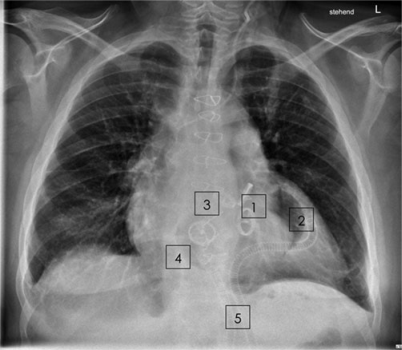

Abb. 6

Röntgenuntersuchung des Thorax am 78. postoperativen Tag vor Entlassung: 2 Kippscheibenprothesen (1) des linken Ventrikels (2); 2 Kippscheibenprothesen (3) der rechten Pumpkammer (4); Druckleitungen durch die Bauchdecke (5)